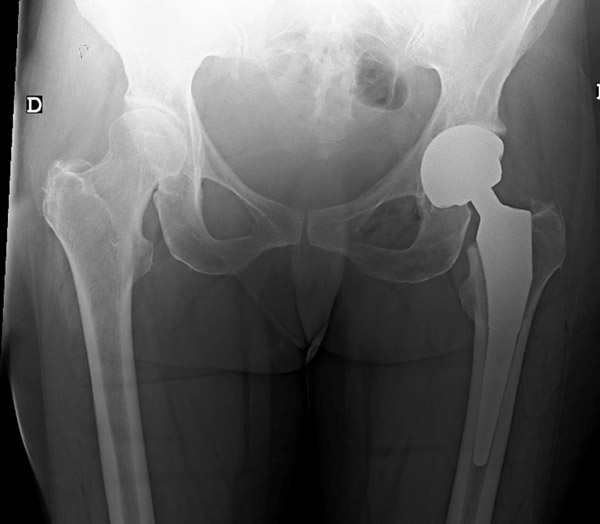

Final strategy decision : Total Hip Replacement

• Total Hip Replacement ✔️

Final strategy decision